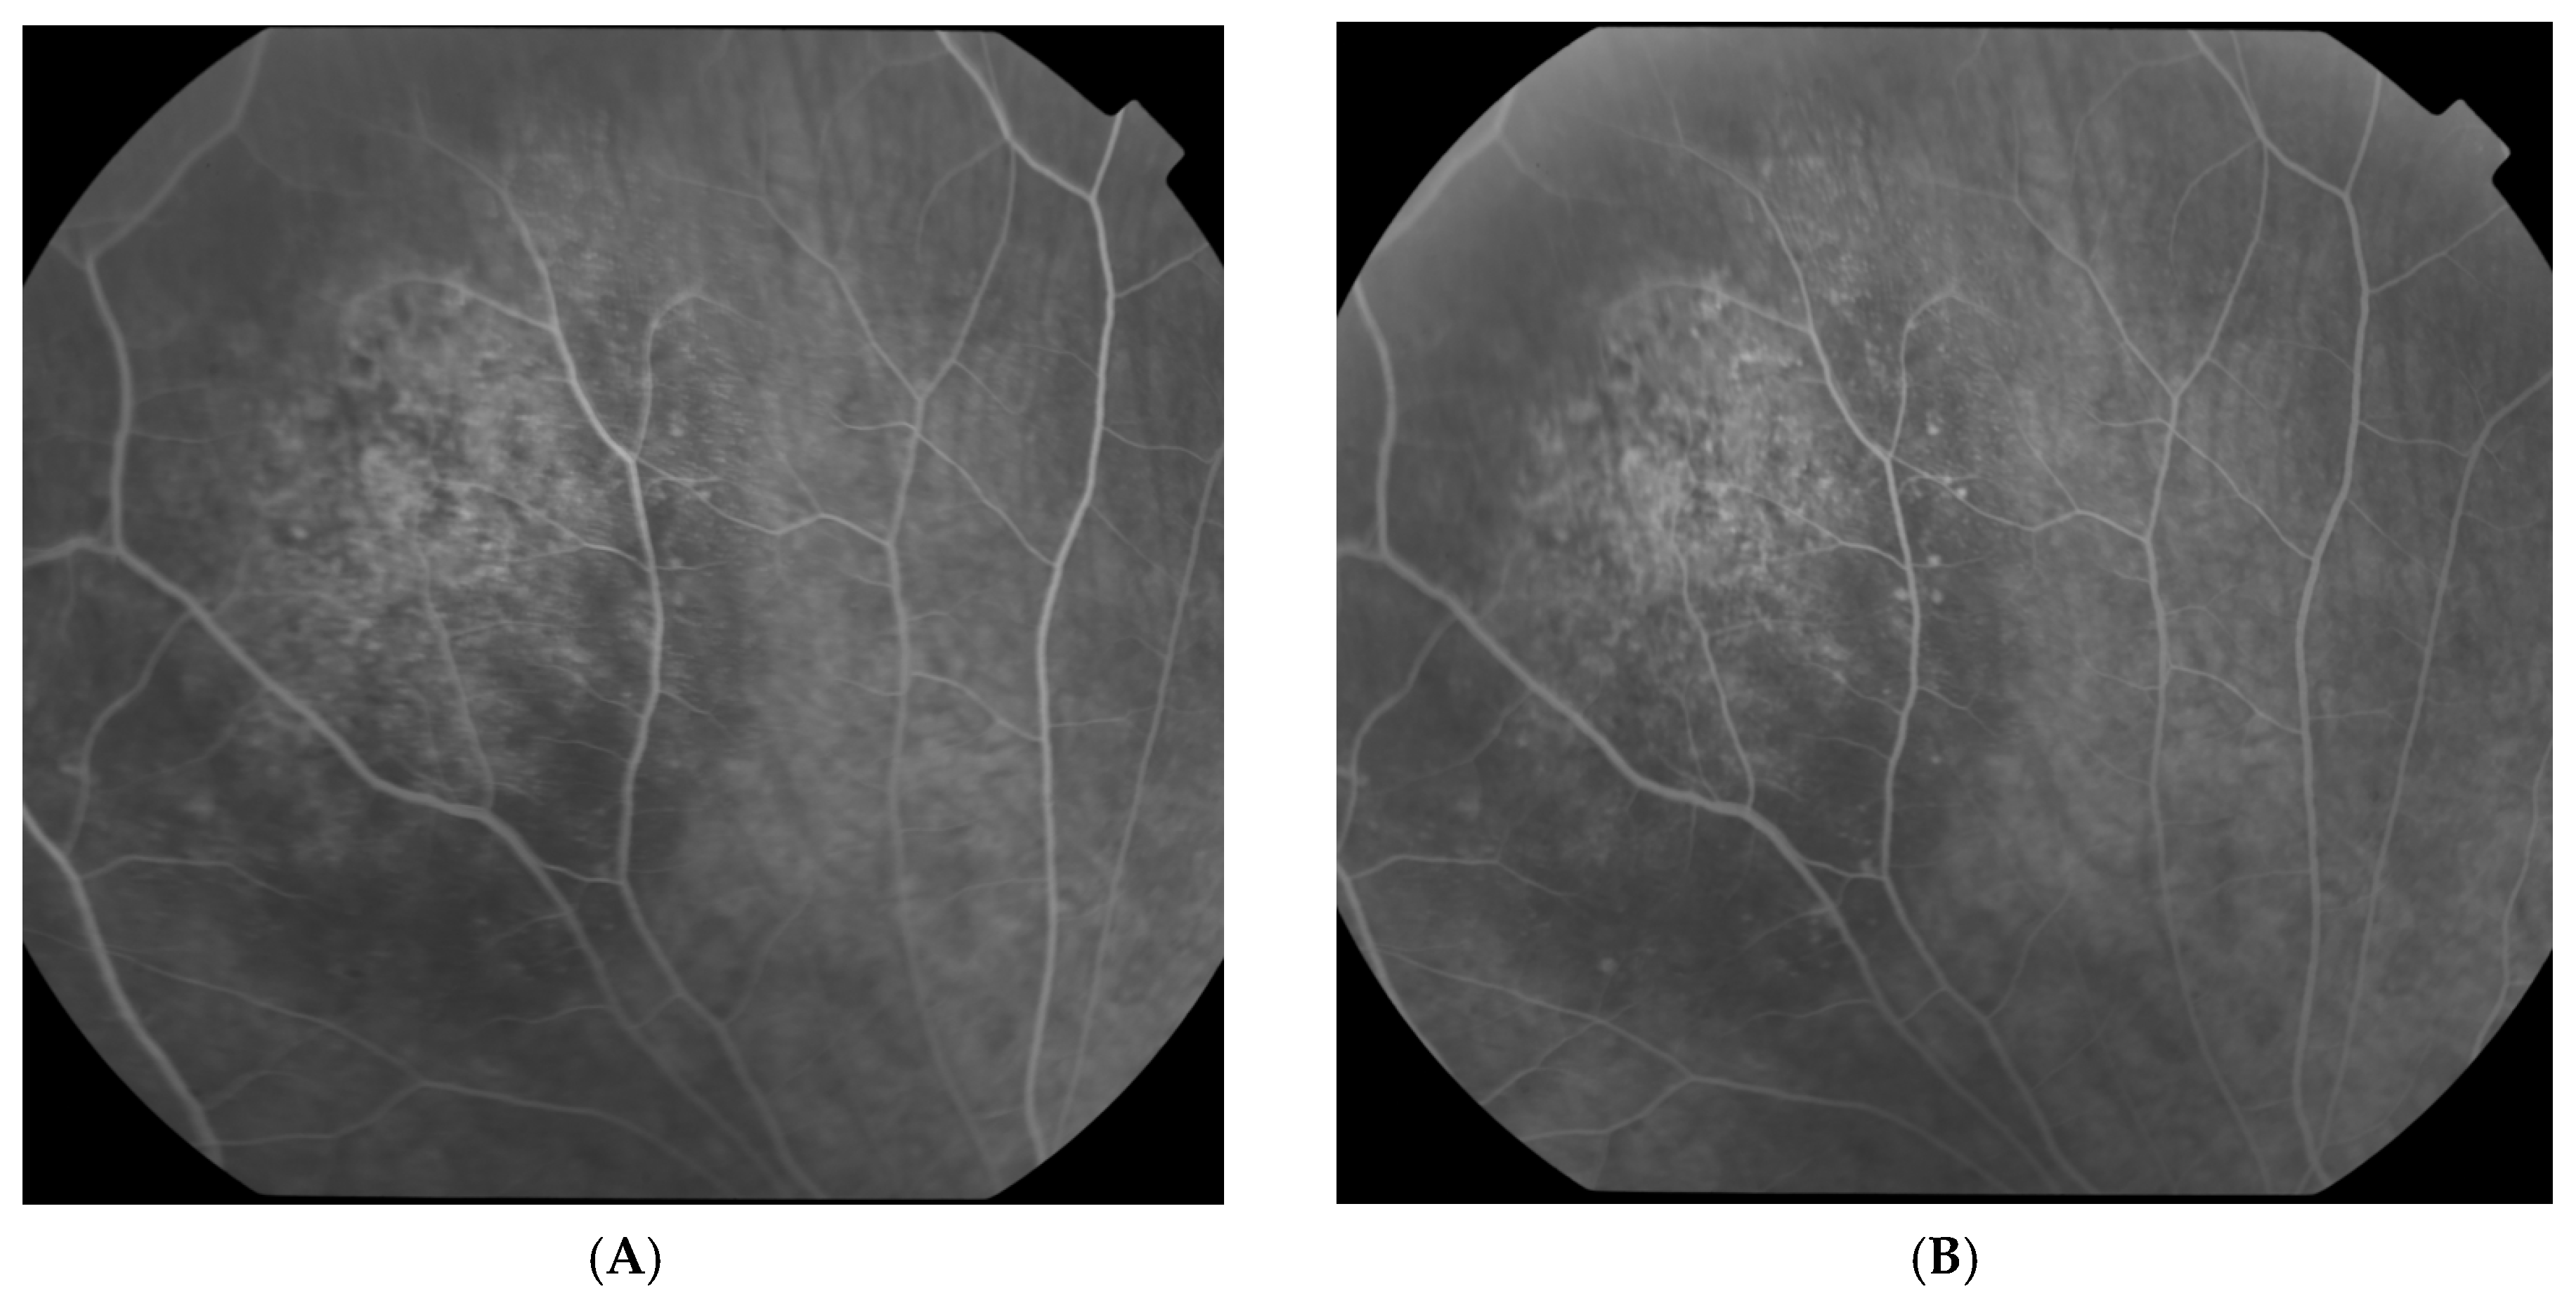

2.2. Clinical Findings

2.3. Diagnostic Assessment